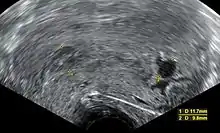

Ultrasound criteria

A review article in The New England Journal of Medicine based on a consensus meeting of the Society of Radiologists in Ultrasound in America (SRU) has suggested that miscarriage should be diagnosed only if any of the following criteria are met upon ultrasonography visualization:[97]

| Miscarriage diagnosed | Miscarriage suspected | References |

|---|---|---|

| Crown-rump length of at least 7 mm and no heartbeat. | Crown–rump length of less than 7 mm and no heartbeat. | [97][98] |

| Mean gestational sac diameter of at least 25 mm and no embryo. | Mean gestational sac diameter of 16–24 mm and no embryo. | [97][98] |

| Absence of embryo with heartbeat at least 2 weeks after an ultrasound scan that showed a gestational sac without a yolk sac. | Absence of embryo with heartbeat 7–13 days after an ultrasound scan that showed a gestational sac without a yolk sac. | [97][98] |

| Absence of embryo with heartbeat at least 11 days after an ultrasound scan that showed a gestational sac with a yolk sac. | Absence of embryo with heartbeat 7–10 days after a scan that showed a gestational sac with a yolk sac. | [97][98] |

| Absence of embryo at least 6 weeks after last menstrual period. | [97][98] | |

| Amniotic sac seen adjacent to yolk sac, and with no visible embryo. | [97][98] | |

| Yolk sac of more than 7 mm. | [97][98] | |

| Small gestational sac compared to embryo size (less than 5 mm difference between mean sac diameter and crown-rump length). | [97][98] |